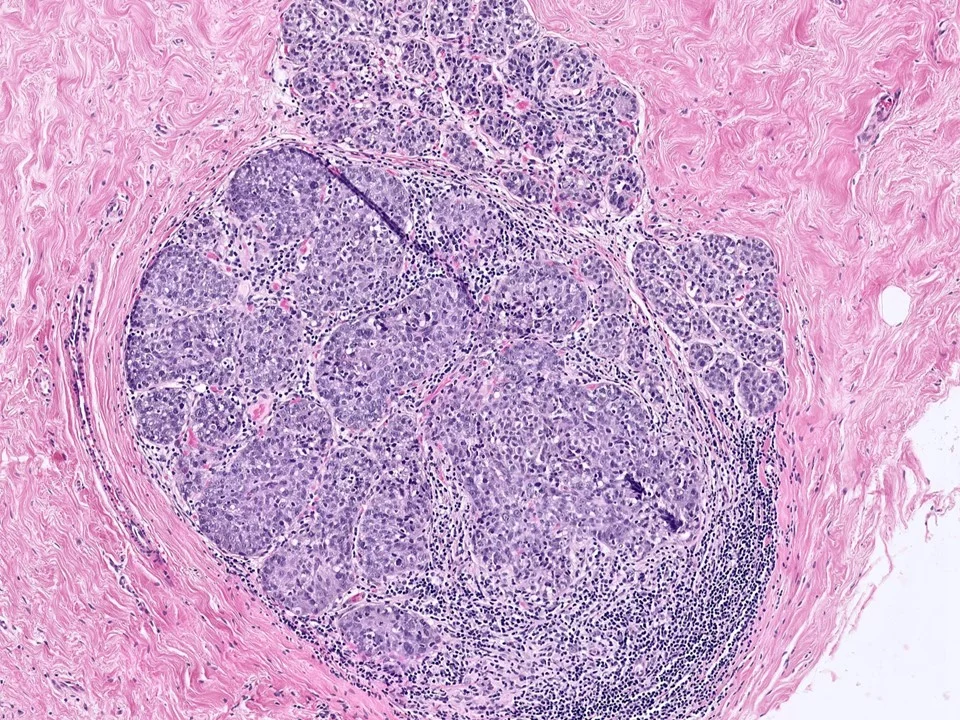

Invasive Ductal Carcinoma, Grade 3, With Extensive Lymphovascular Invasion

Invasive ductal carcinomas are the most common type of invasive breast cancer (70-75% of cases). They are heterogeneous with regards to pathologic features and clinical course.

Histologically, IDCs vary with regard to growth pattern (eg tubular vs solid), cytologic features, mitotic activity, stromal desmoplasia, and extent of associated in-situ component. The degree of gland formation, nuclear atypia, and mitotic activity are considered together in determining the combined histologic grade.

Three universally accepted biomarkers are used in daily practice currently: estrogen receptor (ER), progesterone receptor (PR), and HER2. Studies have shown about 70-80% of IDCs are ER+ and 15% show HER3 overexpression.